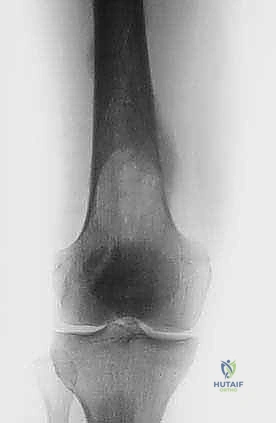

2. استئصال الورم وتغيير المفاصل (Tumor Resection & Endoprosthetic Arthroplasty)

في الحالات التي يدمر فيها الورم المفصل بالكامل (مثل مفصل الورك أو الركبة)، يقوم الدكتور هطيف باستئصال الجزء المصاب من العظم والورم معاً، واستبداله بمفصل صناعي خاص بالأورام (Megaprosthesis). بفضل خبرته الواسعة في تغيير المفاصل، يستطيع المريض المشي في اليوم التالي للعملية!

| عظم الفخذ (القسم العلوي) | كسر عنق الفخذ، العجز عن المشي. | استبدال مفصل الورك بمفصل صناعي (Arthroplasty). |